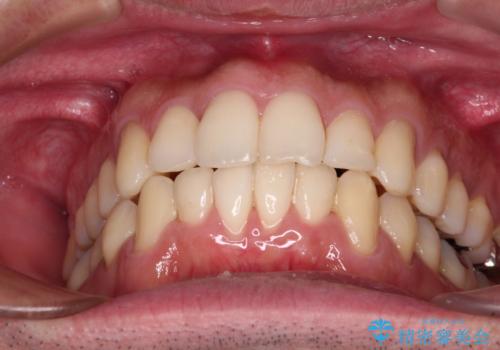

下顎骨が顕著に右側にずれている インビザラインによる咬合改善

- 上下前歯のデコボコを気にして来院された患者様です。

下顎骨が顕著な左右差を持って成長したため、右側にずれている状態でした。

デコボコは抜歯をすることなく解消できる程度であったため、インビザラインにより矯正治療を行うこととしました。